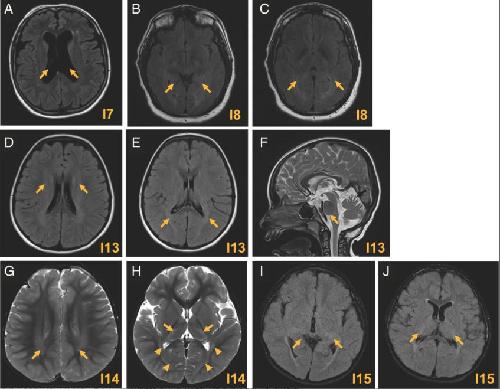

HCN2-Associated Neurodevelopmental Disorders: Data from Patients and Xenopus Cell Models.,

Houdayer C,Phillips AM,Chabbert M,Bourreau J,Maroofian R,Houlden H,Richards K,Saadi NW,Dad'ová E,Van Bogaert P,Rupin M,Keren B,Charles P,Smol T,Riquet A,Pais L,O'Donnell-Luria A,VanNoy GE,Bayat A,Møller RS,Olofsson K,Jamra RA,Syrbe S,Dasouki M,Seaver LH,Sullivan JA,Shashi V,Alkuraya FS,Poss AF,Spence JE,Schnur RE,Forster IC,Mckenzie CE,Simons C,Wang M,Snell P,Kothur K,Buckley M,Roscioli T,Elserafy N,Dauriat B,Procaccio V,Henrion D,Lenaers G,Colin E,Verbeek NE,Van Gassen KL,Legendre C,Bonneau D,Reid CA,Howell KB,Ziegler A,Legros C,

Ann Neurol. September 5, 2025; 98(3):1531-8249.